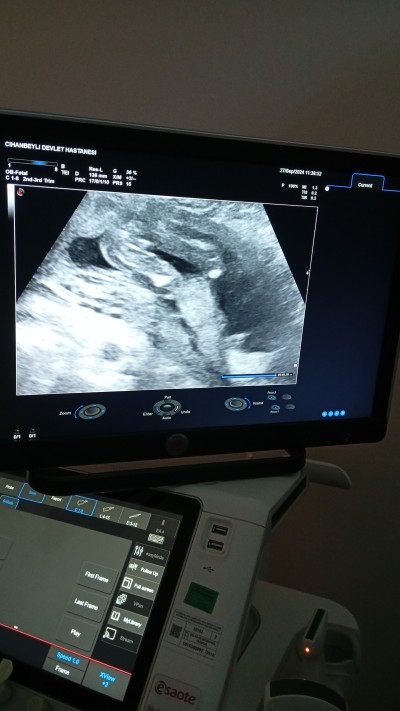

Benim ilk 16haftalikken çıkıntı var gibi dedi dün gttim doktora kız dedi 19haftaligim şuanda bacak arasını net girdi ama zorla gördük bir türlü açmadı bacağını arkasından bkti doktor öyle gördü buraya ultrason resimlerini atmıştım herkes bana erkek dedi nub teorisine göre dediler.bnde iki oğlum var hep kızım olsun istemiştim şükür oldu buda dün ben kndim doktorun ultrasonun dan cektim doktor çıkınca

image